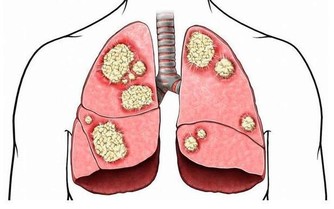

便血不止是痔瘡的常見病症,結直腸癌患者也會出現類似情況,

因此發現大便帶有血跡時,要盡快去醫院確診病因。

已經被確診的痔瘡患者,應當遵照醫囑服用藥品,在飲食和作息上都要進行一定的調整。

病情比較嚴重時,患者可能需要通過手術來緩解病痛,具體事宜要應從專業醫護人員的安排。

身體素質較好的人,也需要定期體檢,儘早排除健康隱患。